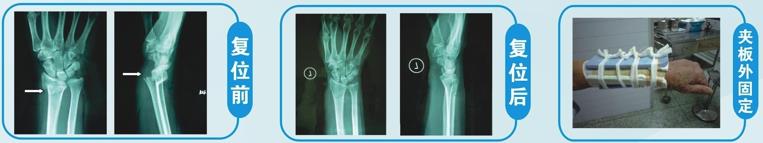

(1)桡骨远端骨折 临床上最常见的骨折之一,多因跌倒时手掌撑地引起,常见于老年人,可造成严重粉碎性骨折,治疗不当容易遗留腕部畸形,影响手腕功能。科室治疗这类骨折经过丰富,手法复位快速准确,夹板固定轻便稳固,能最大程度恢复患者手腕功能。